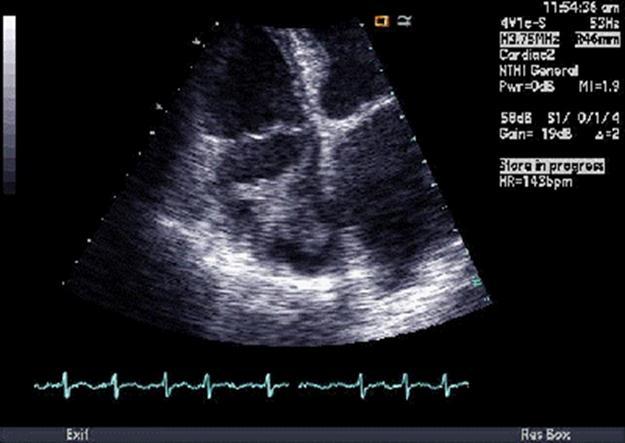

87 year old female from nursing home was admitted to Coronary Care Unit (CCU) because of atrial fibrillation with rapid ventricular rate. Heart rate was controlled with digoxin and metoprolol and continued on warfarin. Echocardiogram showed a highly mobile right atrial thrombus (Figure 2), left ventricular ejection fraction 40-45%. Six days later, echo and magnetic resonance imaging (MRI) did not show the thrombus; however, CT of the chest showed emboli in the pulmonary arterial branches of the right middle and right lower lobes. Venous duplex showed acute deep venous thrombosis in the right leg. No ABG was done. Blood analyses showed glucose 99, BUN/Cr 15/0.5, Na 137, K 3.4, Ci 107, bicarbonate 24, Ca 8.4, albumin 2.2, three sets of cardiac enzymes (CKMB & CTNI) within normal limits, WBC 7.6, hemoglobin 9.2, hematocrit 27, platelets 134, fecal occult blood negative. Inferior vena cava (IVC) filter was placed under fluoroscopic guidance before discharging the patient on digoxin and warfarin.

Figure 2.Echographic image of Case 2 of the large, mobile thrombus in the right atrial cavity.